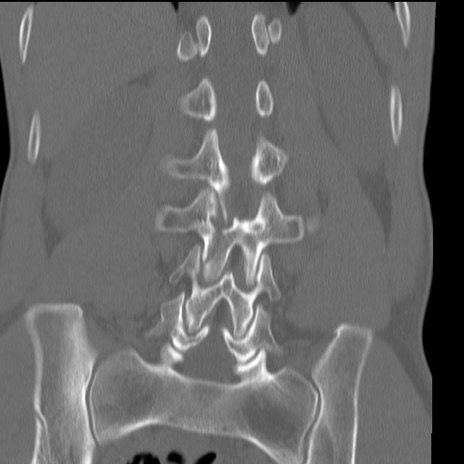

症例3 腰椎CT(冠状断像)

【症例】30歳代男性

【主訴】腰痛

【現病歴】本日旅行先で観光中に、友人と衝突し転倒し受傷。

【身体所見】麻痺なし、右下腿内側前面外側、左下腿内側に知覚鈍麻・しびれ

異常所見と診断は?

腰椎CT